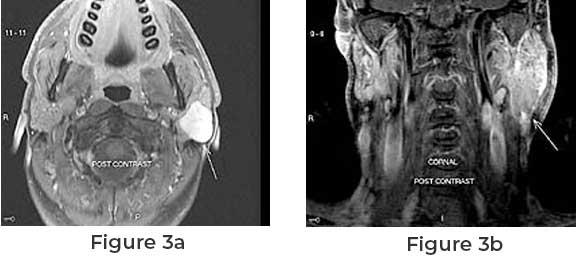

Swelling or Lump – The most common symptom of parotid cancer is the development of a painless lump or swelling in the area of the parotid glands. This can be noticed in front of or just below the ear.

Facial Weakness or Numbness – As the tumor grows, it may press on facial nerves, leading to weakness or numbness on one side of the face.